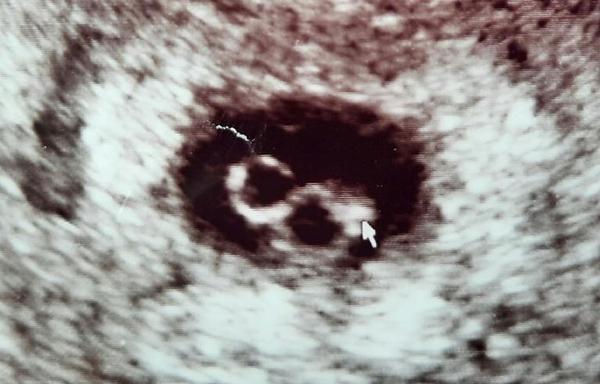

Embryo vpravo má 4,5 mm a srdeční akci, maličké embryo vlevo srdeční akci nemá. Ultrazvuk pořízen cca 7+3, ale velikostně vitální embryo odpovídá méně.